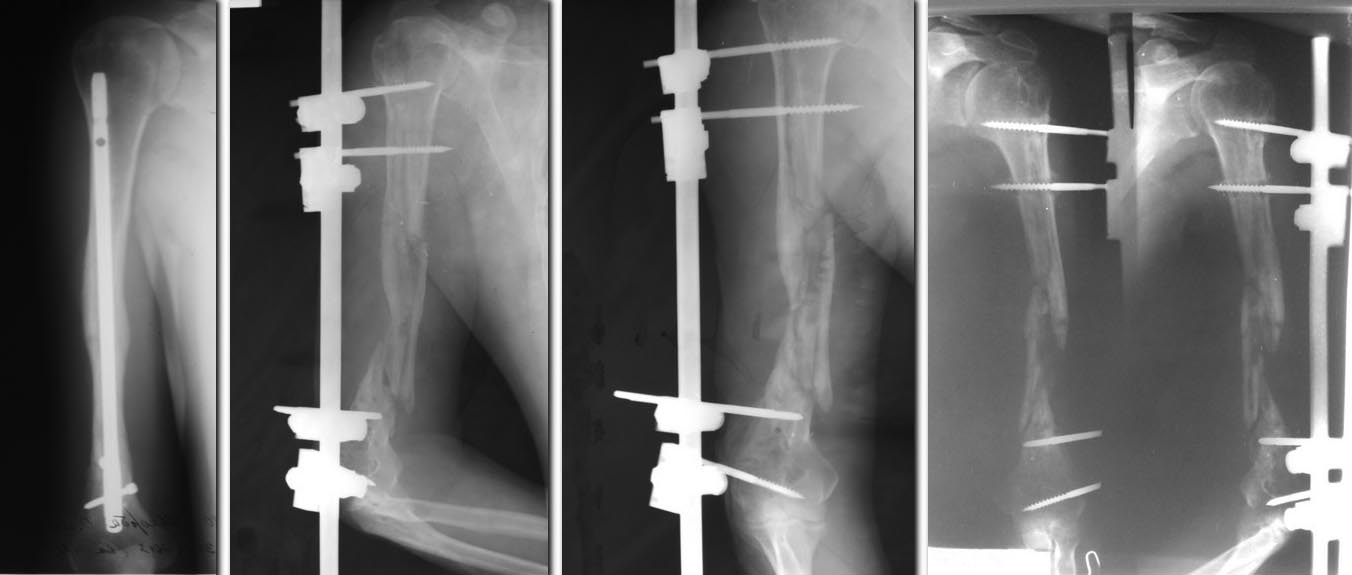

Поступил пациент 39 лет. В анамнезе в марте 2013 года в одном из

медицинских учреждений произведено удаление интрамедуллярного стержня из

левой плечевой кости. По выписке - при удалении были технические

трудности, что привело к перелому плечевой кости. Перелом фиксирован

аппаратом внешней фиксации (фото 2 и 3). На данном этапе отмечается

нестабильность аппарата (фото 4), расшатывание проксимальных стержней,

патологическая подвижность в месте перелома. Воспаления вокруг стержней

нет, свищей нет. Аппарат демонтирован для заживления ран от стержней.

Рассматривается вариант оперативного лечения - фиксация перелома LCP

пластиной с костной пластикой. Интересует мнение коллег в плане

технических моментов операции и возможных альтернативных методов лечения

данного пациента.